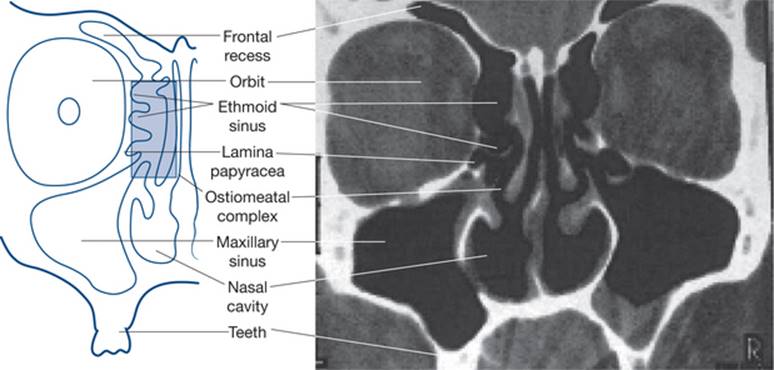

The nose and sinuses are made up of a number of components (Figs 2.11 and 2.12).

• The nasal airway comprises a midline septum and a lateral nasal wall. The septum has a cartilaginous component and a bony component made up of the perpendicular plate of the ethmoid and the vomer. There are also contributions from the maxilla and palatine bones.

• The lateral nasal wall comprises the ethmoid bone and its turbinates — superior and middle, the inferior turbinate, the maxilla, lacrimal and palatine bones.

• The sphenoid sits at the postero-supero-lateral aspect of the nasal airway.

• The roof of the nose comprises the ethmoid, the cribriform plate and the sphenoid.

• The floor of the nose is made up of the maxilla and the palatine bone.

• The nose and paranasal sinuses are lined by respiratory epithelium — ciliated columnar epithelium, which is secretory. The daily secretions of the nose and paranasal sinuses is in the order of 800 mL per day.

• The function of the turbinates is to warm and humidify inspired air.

Figure 2.11 Structure of lateral nasal wall

From Dhillon & East, 2006

Figure 2.12 Paranasal sinuses